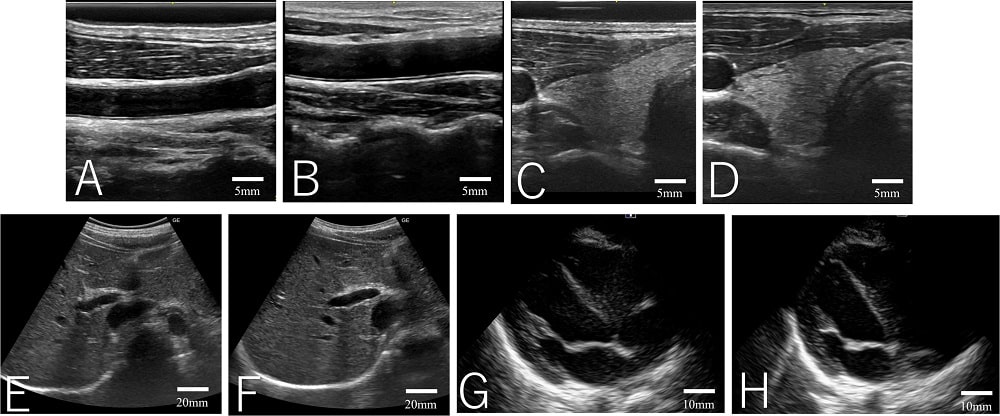

Эффективность подушечки протестировали на четырех здоровых добровольцах: они прошли УЗИ, в рамках которых визуализировались разные типы тканей. Качество изображения во всех случаях было сопоставимо с качеством, которое обеспечивает обычный жидкий гель. При этом добровольцы чувствовали себя комфортнее: влага, которую выделяла подушечка, не прилипала к волосам на теле и легко удалялась.